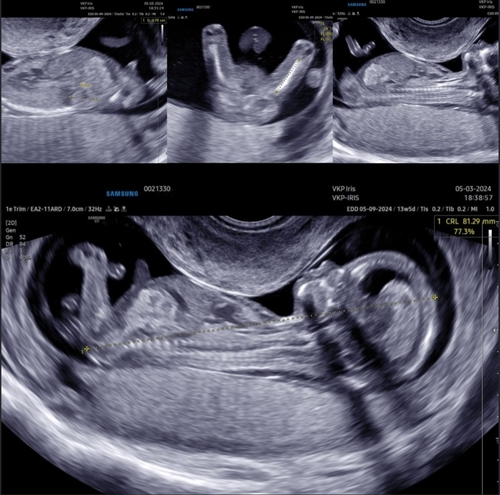

Ik zet hem voor de zekerheid ook even in deel 2! 13 weken en 2 dagen op deze echo ❤️

Ik zet hem voor de zekerheid ook even in deel 2! 13 weken en 2 dagen op dez ...

Helaas geen nub te zien